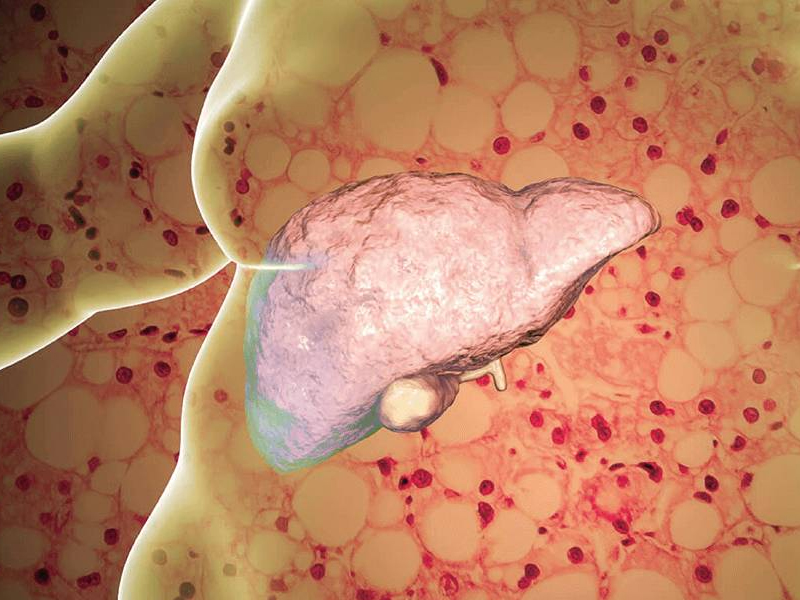

癌症不是一日就長成的,有一個相當長的過程。很多癌症有癌前狀態,有一些良性病變其實是惡性腫瘤的“前奏”,如不重視,任其發展下去,有可能演變成癌症。 小病不治成大病,所謂大病者,其中之一就是惡性腫瘤。以下幾種小病不重視可能拖成癌症。 1、慢性炎症 ① 反流性食管炎增加食管癌風險。 ② 慢性萎縮性胃炎有發展為胃癌的風險。 ③ 慢性潰瘍性結腸炎(據估計有 3%~5% 的潰瘍性結腸炎發生大腸癌,潰瘍性結腸炎史 20 年,發生癌變者 12.5%,30 年時達 40%)。 ④ 慢性肝炎,病毒性肝炎(主要是慢性乙肝和丙肝)是原發肝細胞肝癌的主要危險因素,其他酒精性肝炎、藥物性肝炎也是危險因素。 ⑤ 慢性胰腺炎,可損傷胰腺實質,反復發生可使胰腺癌發病率上升。 ⑥ 膽道系統慢性炎症,是膽囊癌膽管癌的危險因素。長期慢性膽囊炎引起的磁性膽囊,22% 存在膽囊癌。西方國家原發性硬化性膽管炎是膽管癌最重要的危險因子,8%~40% 的原發性硬化性膽管炎患者合併膽管癌。 ⑦ 膀胱感染(寄生蟲、細菌、真菌或病毒感染)可能增加膀胱癌風險。 ⑧ 前列腺的慢性炎症,可導致細胞過度增殖以修復病變組織,易形成感染相關性癌症。流行病學研究顯示患性病或前列腺炎病史的患者,患前列腺癌的風險明顯增高。 ⑨ 包皮陰莖頭慢性炎症,是陰莖癌的發病危險因素。 2、慢性阻塞性肺疾病 研究表明,有慢性支氣管炎者,肺癌發病率高於無慢性支氣管炎者(幾乎2倍)。其他如肺結核病史、肺炎和肺氣吸等都和肺癌有一定的關聯。 3、胃腸道息肉 有大約 15%~40% 的結腸癌源於結腸多發性息肉,其癌前期病程約為 5~20 年;腺瘤可以癌變,直徑小於 1cm 者癌變率低於 2%,直徑大於 3cm 癌變率超過40%。而如果是家族性腺瘤性息肉病(FAP)患者,25 歲時惡變率為 9.4%,30 歲為 50%,50 歲以前幾乎 100% 惡變,中位惡變年齡為 36 歲。 4、結石 膽管結石,膽囊結石是膽管癌膽囊癌的主要危險因素之一。膽囊結石和膽囊癌之間有很強的關聯性,75% 的膽囊癌患者合併膽囊結石,直徑超過 3cm 的膽囊結石患者,膽囊癌風險上升 10 倍。 膀胱結石可能增加膀胱癌風險。 5、白斑性病變 口腔黏膜白斑或紅斑是口腔癌的風險因素。外陰白斑可能是外陰癌的風險因素之一。 6、潰瘍性病變 胃十二指腸潰瘍可能發展為胃癌。口腔潰瘍經久不愈要警惕口腔癌。任何部位的潰瘍如果經久不愈,都要提高警惕。 |